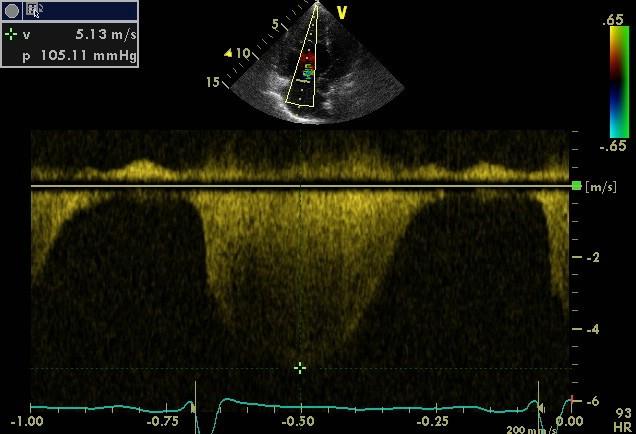

Echokardiografie: LEVÁ KOMORA bez dilatace a hypertrofie, s normální systolickou funkcí a regionální kinetikou kromě D shape, EF LK 55-60%. Diastolická funkce: porucha relaxace LK. PRAVÁ KOMORA FAC PK 18%, TAPSE 13 mm, Vt 9 cm/s, dilatace a hypertrofie PK, těžká prekapilární PH, odhadovaný PASP 90 mmHg, MPAP 55 mmHg, malý perikardiální výpotek

Hemodynamika: PS: 18 mmHg, spO2 53,6%, PK: 93/8 mmHg, AP: 99/43/60 mmHg, PAWP: 13 mmHg (střední), PVR: 13,8 WU, CO: 3,04 l/min., CI: 1,6 l/min./m2

Echokardiografie: LEVÁ KOMORA bez dilatace a hypertrofie, s normální systolickou funkcí a regionální kinetikou kromě D shape, EF LK 55-60%. Diastolická funkce: porucha relaxace LK. PRAVÁ KOMORA FAC PK 19%, TAPSE 17 mm, Vt 9 cm/s, dilatace a hypertrofie PK, těžká prekapilární PH, odhadovaný PASP 130

mmHg, perikardiální výpotek